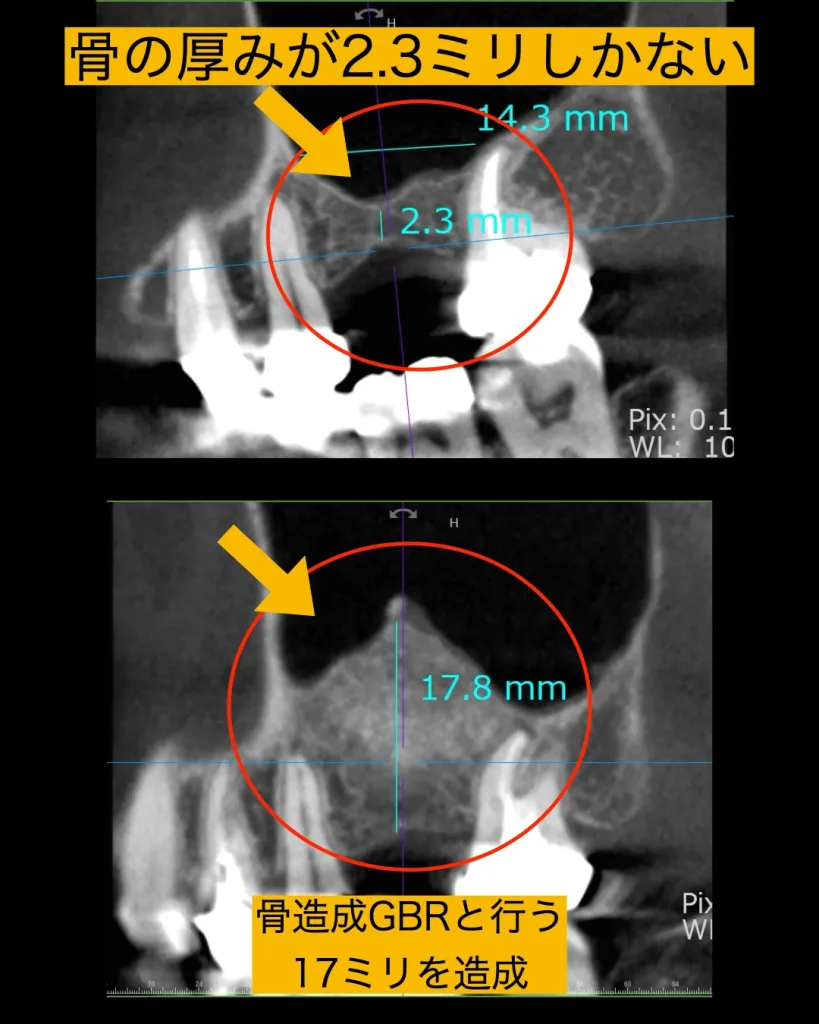

サイナスリフトを行う前の骨は2.3ミリほどしかありませんでしたが、骨造成を行ったあとは17.3ミリほどに増加しました。

サイナスリフトとは上顎の頬部の空洞の粘膜を押し上げて骨造成を行う方法であり、難易度の高い歯周外科の一つの手技です。サイナスリフトを行ったあと、6ヶ月の骨硬化を待ちました。